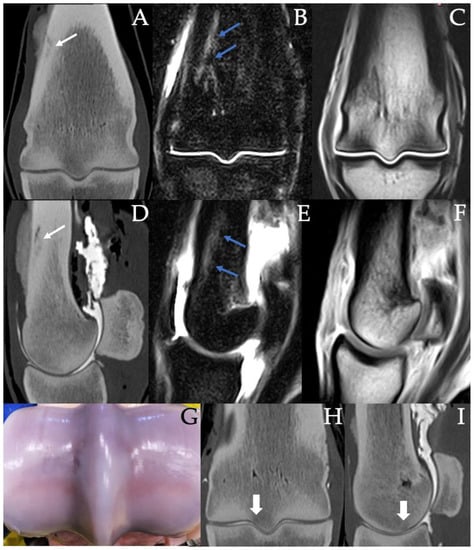

3.2. Sclerosis of the Subchondral and Adjacent Medullary Bone of the PSGs

3.3. PSG Subchondral Bone Lysis

3.4. PSG Subchondral Bone Defects

3.5. PSG Cartilage Defects

3.6. PSG STIR Hyperintensity